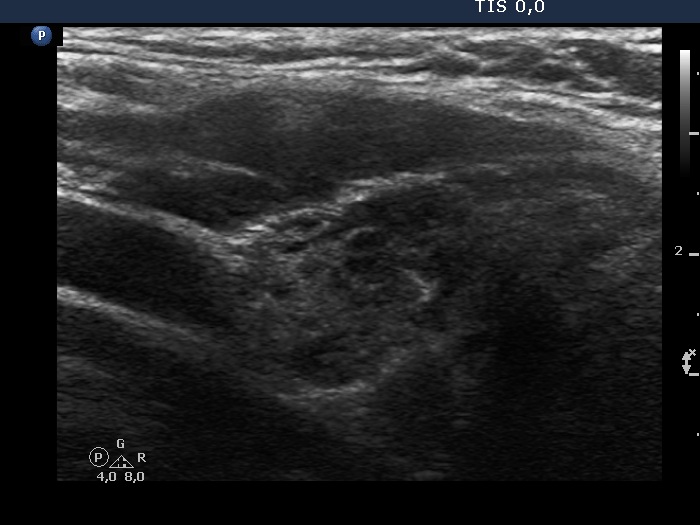

Right lobe, longitudinal scan

Left lobe, longitudinal view - set to better penetrance. The dorsal parts of the lobe are better visible with this setting.